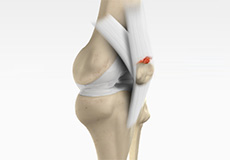

Osteochondral Defect of the Knee

An osteochondral defect, also commonly known as osteochondritis dissecans, of the knee refers to a damage or injury to the smooth articular cartilage surrounding the knee joint and the bone underneath the cartilage. The degree of damage may range from a rupture of the cartilage to a slight crack of the bone to a piece of the bone breaking off within the joint.